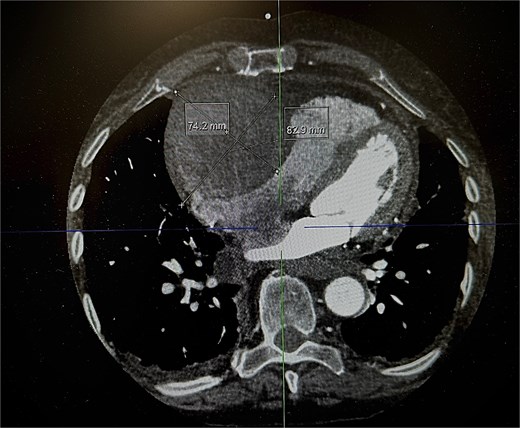

An 82-year-old female presented to the emergency department complaining of progressive severe central chest that was pleuritic in nature, radiating to her right arm. Following a bedside echo, the patient underwent coronary angiography, where a giant right CAA was diagnosed (Fig. 1). Subsequent, contrast computed tomography (CT) scan further characterized the aneurysm, and highlighted significant compression was uncovered compressing both the right atrium and ventricle (Fig. 2). The right coronary aneurysm was measured cross-sectional dimensions of 8.3 × 7.4 cm (Fig. 3) and 10 cm in length (Fig. 4). Following Heart Team discussion, the patient was scheduled for an aneurysmectomy and coronary artery bypass to repair the extensive disease.

Axial plane of a contrast thorax CT scan showing the giant right coronary aneurysm.